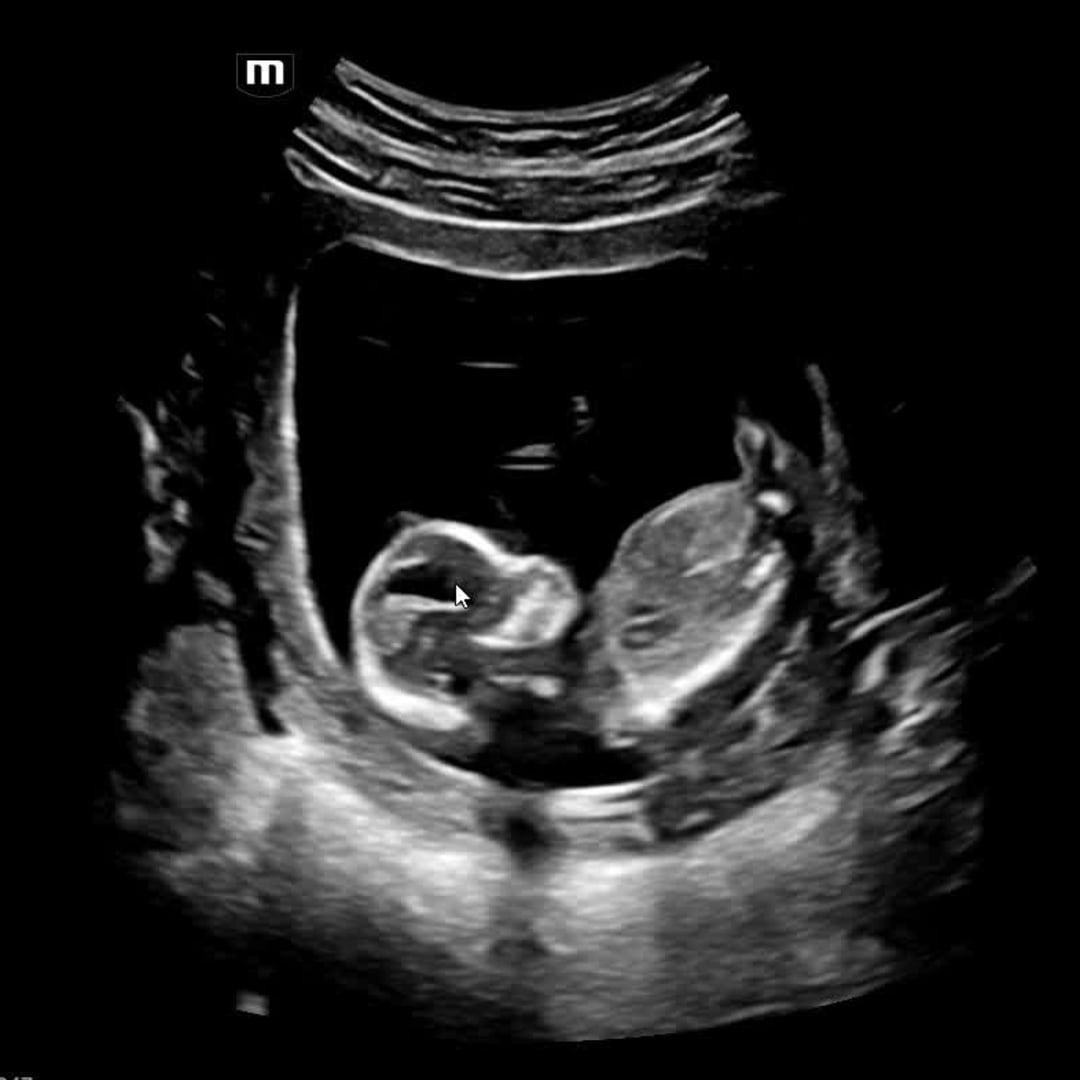

We are so grateful for the love and support surrounding our growing family. As we prepare to welcome our little one, we’re filled with excitement, joy, and deep appreciation for each of you who has shared in this journey with us.

Your kindness—whether through prayers, well wishes, or thoughtful gifts—means more to us than words can express. Thank you for helping us get ready for this beautiful new chapter. Our baby is already so loved, and we feel incredibly blessed to have such wonderful people in our lives.Nursery & decor